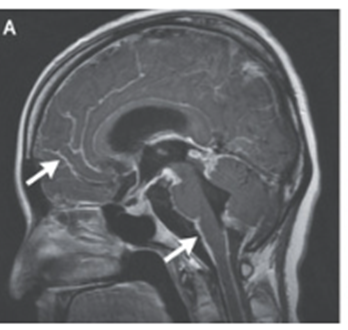

頭部造影MRIではT1強調画像で、びまん性軟髄膜高信号を認めた。

続いて腰椎穿刺が行われた。開始時の圧は水柱330mm(基準80~180)だった。

症状を伴う頭蓋内圧亢進症が持続したため、外部の右室ドレーン留置が選択された。